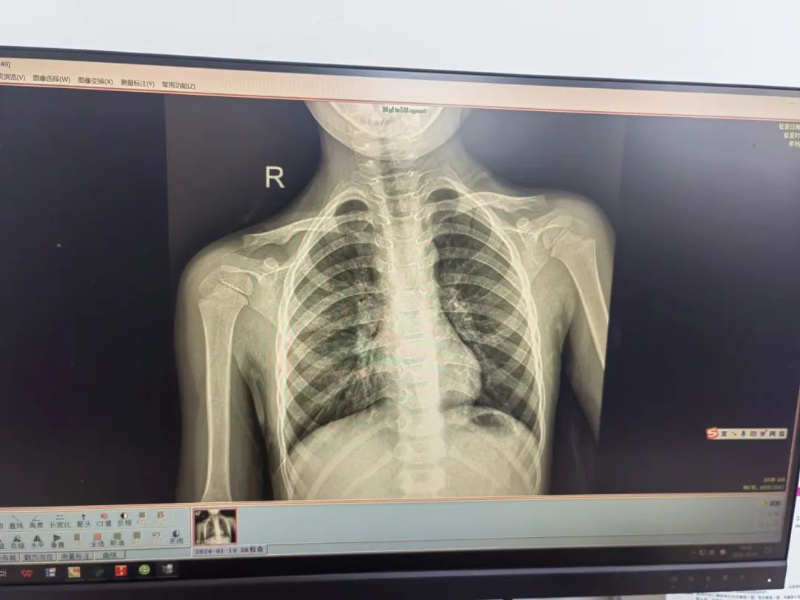

治疗前(左)、后(右)胸片对比

经过9天的精心治疗,帆帆的咳嗽和高热症状已完全消失。在出院前,护士们和家属详细讲解了出院后的注意事项和防护措施,确保帆帆能够在出院后继续得到良好的护理和康复。家属对医生的治疗效果和贴心服务表示衷心的感谢,并手写一份感谢信赠与医护人员。